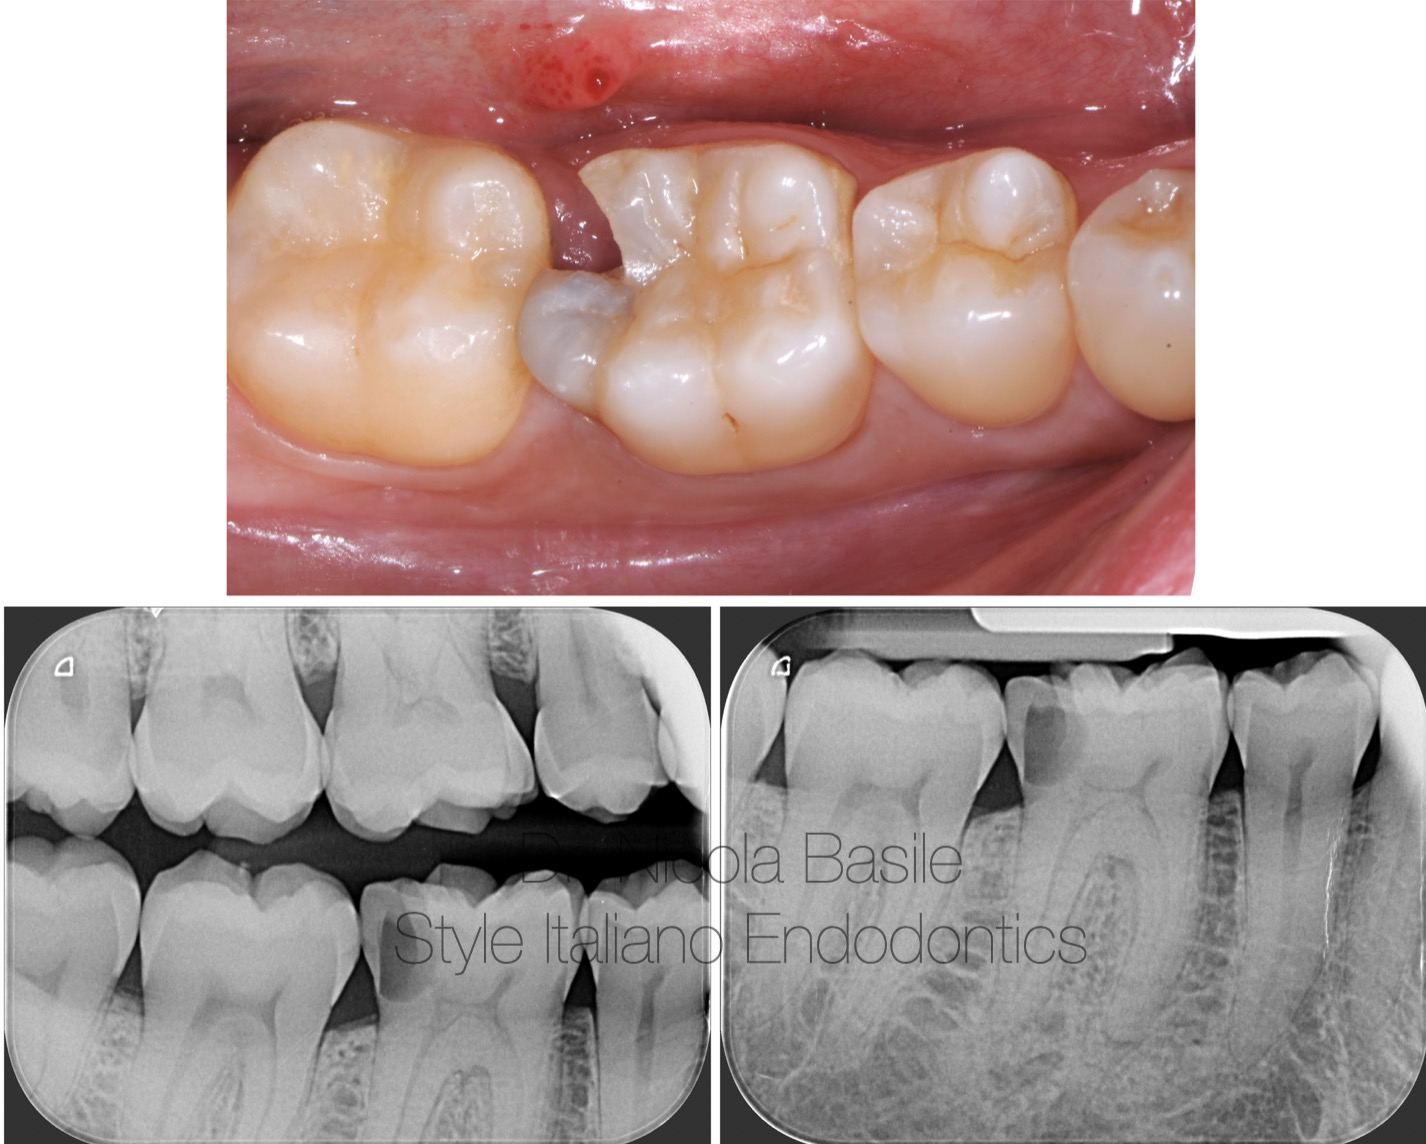

Fig. 13

Control Xray

Fig. 14

Before and after.

The case was completed within 8 days.

It was important to have a few more days to also obtain positive feedback from the patient during mastication before departure.

Fig. 15

Follow up 3 years